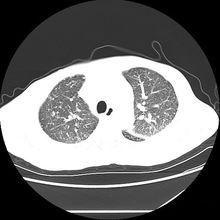

肺鈣化灶肺炎性鈣化CT表現(圖3):淋巴細胞性間質性肺炎。軸向 CT 顯示(肺窗):多發囊腫伴部分實質結節;圖 b 左肺外周可見鈣化結節;活檢證實為澱粉樣變。